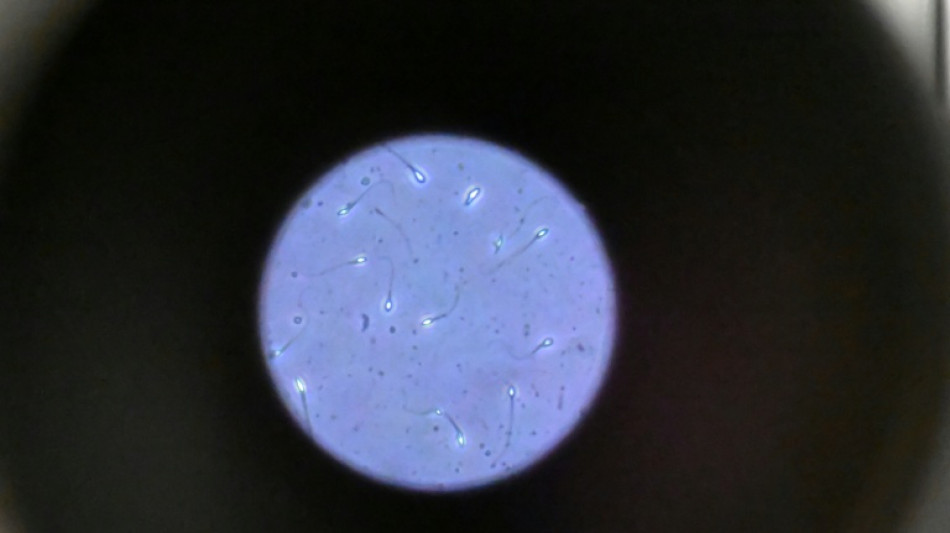

Dans l'espace, les spermatozoïdes ont du mal à trouver leur chemin / Photo: © AFP/Archives

Dans l'espace, les spermatozoïdes ont du mal à trouver leur chemin vers l'ovule en raison de la microgravité, qui perturbe aussi le développement des embryons, selon une étude publiée jeudi dans Communications Biology.

Une des difficultés réside dans le fait que le sperme n'est plus attiré vers le bas par la gravité terrestre.

Les chercheurs ont testé successivement du sperme de souris et humain dans ce dispositif placé dans un appareil en constante rotation pour simuler la microgravité.

Les gamètes ont été environ 50 % moins performants pour naviguer à travers ce parcours que sous la gravité terrestre. Cela équivaut à une baisse de 30% du taux de fécondation réussie, selon les résultats de l'étude.